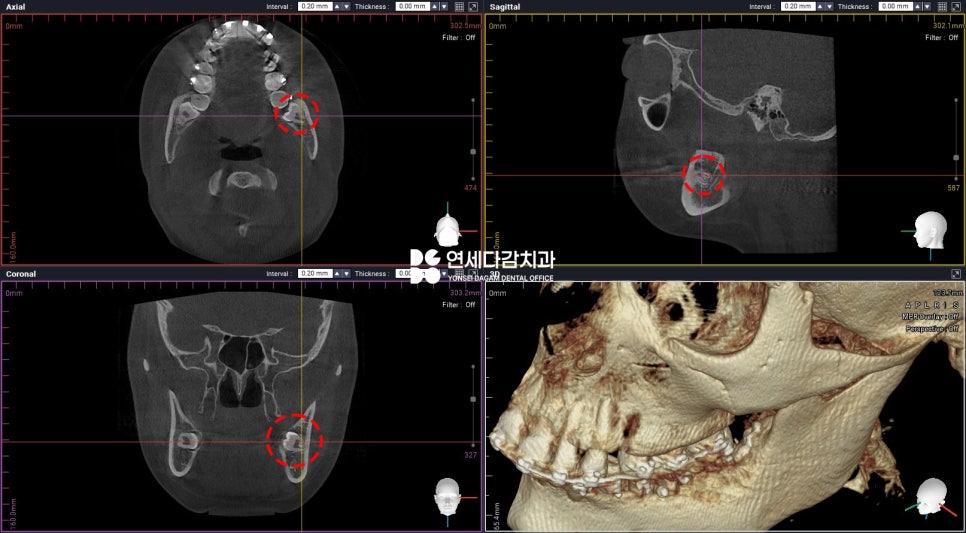

CT를 살펴보면 교합면(치아의 윗면)이

설측으로 수평 매복된 형태였습니다.

설측 점막에는 특히

신경과 혈관이 밀접해 있기 때문에

절개 및 박리 시 주의해야 됩니다.

무리한 접근 시 감각 저하 등의

부작용이 생길 수 있기 때문입니다.

따라서 오금동 치과 에서는

위치를 면밀하게 분석한 뒤

안전한 절개 방법으로 접근하여

섬세한 박리를 통해

조심스럽게 진행했습니다.

그 결과 안정적으로 나올 수 있었고,

두 부위 모두 큰 통증이나

부작용 없이 회복되었습니다.